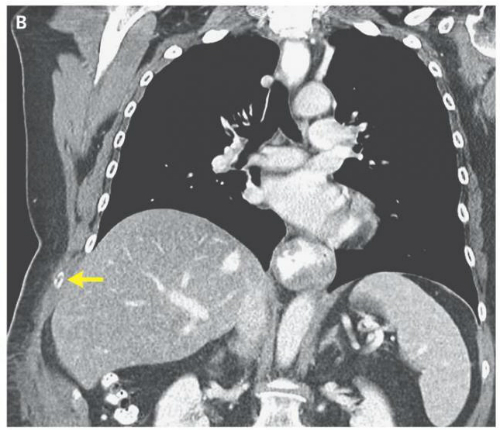

Theo Independent, ca bệnh kỳ lạ này được đăng tải trên tờ New England Journal of Medicine. Ban đầu, nữ bệnh nhân 66 tuổi giấu tên (Mỹ) đi khám vì nghi bị cúm. Năm ngày sau, bác sĩ phát hiện bà bị bầm tím nghiêm trọng ở phần thân bên phải.

Kết quả chụp CT cho thấy nữ bệnh nhân đã bị gãy xương sườn thứ chín vì ho quá mạnh. Kiểm tra thêm, đội ngũ y tế nhận ra bà không hề mắc bệnh cúm mà nhiễm vi trùng Bordetella pertussis gây ho gà. Điều đặc biệt là cách đây tám năm, nữ bệnh nhân đã được tiêm phòng ho gà đồng thời khẳng định không bao giờ tiếp xúc với người mang bệnh.

Ho gà là căn bệnh hiếm khi xảy ra ở tuổi trưởng thành. Triệu chứng ban đầu bao gồm chảy nước mũi, mắt đỏ và chảy nước, đau họng, sốt nhẹ. Sau đó khoảng một tuần, bệnh nhân xuất hiện cơn ho nặng. Ở những ca nghiêm trọng, ho gà có thể dẫn tới các biến chứng như gãy xương sườn.

Nhờ phẫu thuật và thuốc kháng sinh, nữ bệnh nhân 66 tuổi đã hồi phục. Toàn bộ thân nhân cùng nhân viên y tế chăm sóc cho bà cũng được điều trị để đảm bảo không lây ho gà.